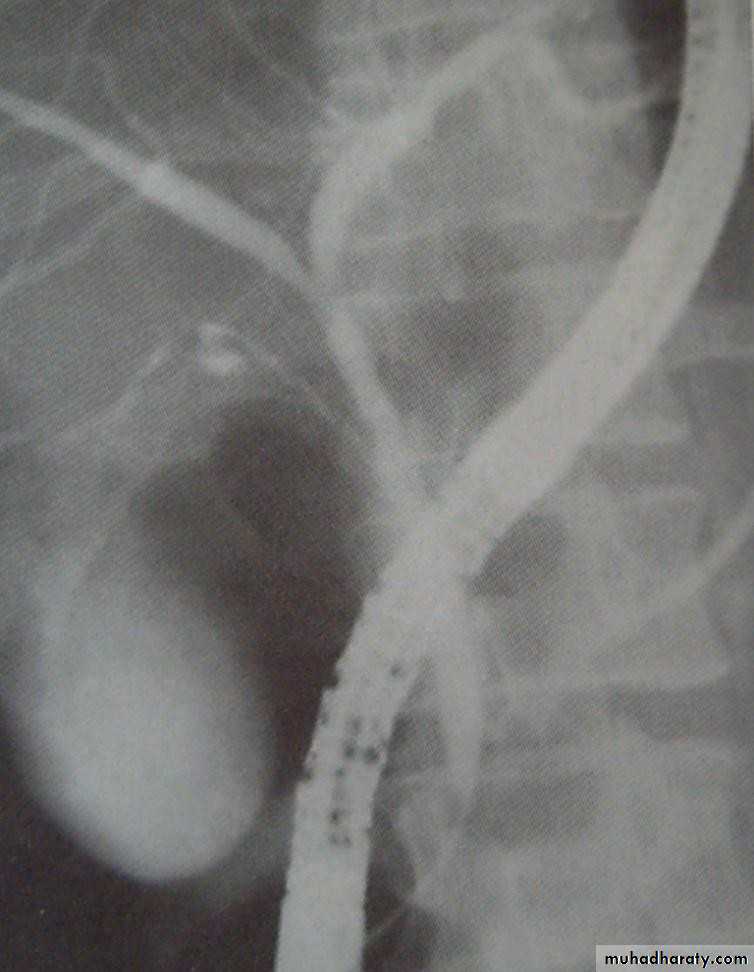

• PERCUTANEOUS TRANSHEPATIC

• CHOLANGOGRAPHY (PTC):

• Preparation;

•  Normal PT

•  Antibiotics

• DX and therapy;

• Visulization of biliary tree

• Placement of; catheter

• Stenting

• choledochoscope

• PTC